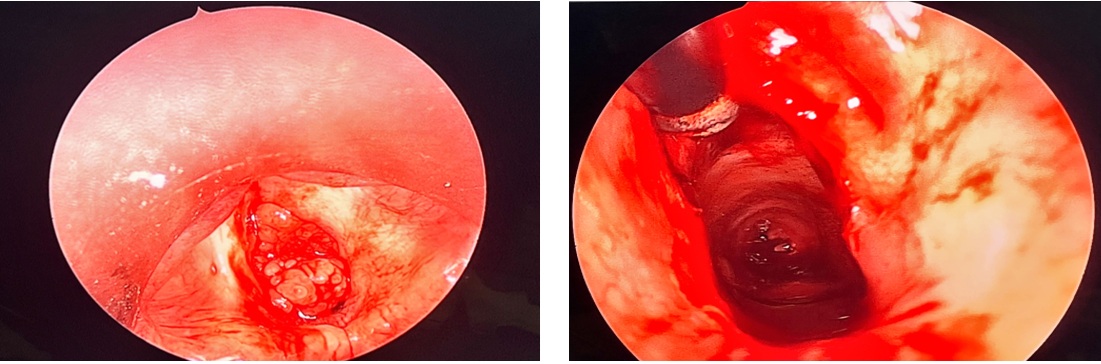

- Tiến hành phẫu thuật: hình ảnh vi phẫu thanh quản cắt u, làm thông thoáng đường thở, kiểm soát chảy máu

Hình 7. Phẫu trường

Hình 10. Kết quả soi sau 10 giờ phẫu thuật